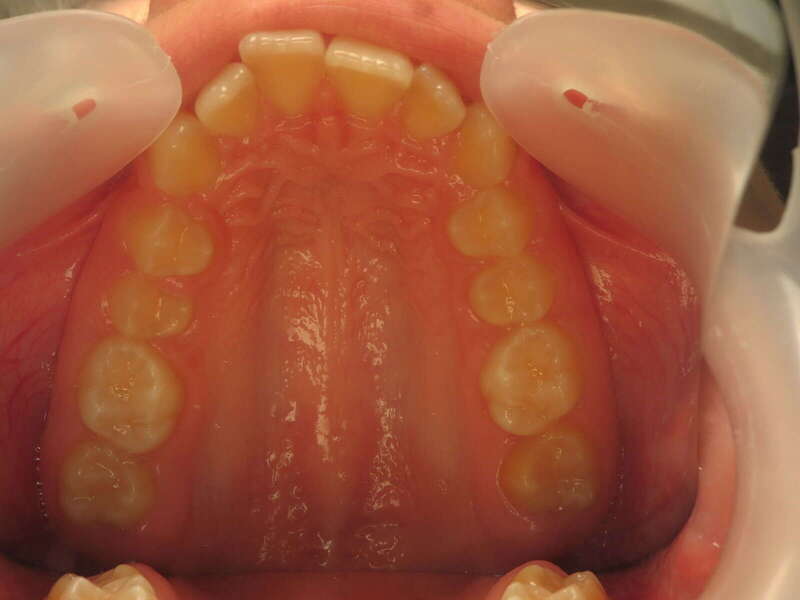

Cas n°9 traité par multi-attaches - adolescent

Ce cas d'adolescent illustre une stratégie de développement d'arcade réussie. Le patient présentait un encombrement massif et des inversions d'articulé rendant l'occlusion instable.

Le traitement a été réalisé avec des multibagues autoligaturantes, choisies pour leur capacité à générer des forces légères et continues, idéales pour l'expansion transversale. Cette approche a permis de corriger l'encombrement et les inversions d'articulé sans extractions dentaires, en remodelant simplement la forme des arcades.

• Transformation d'arcade : Passage d'une arcade étroite et encombrée à une arcade large et fonctionnelle.

• Occlusion optimale : Rétablissement d'un engrènement sain, protégeant les dents contre les usures anormales.

• Esthétique naturelle : Le sourire est élargi, harmonieux et parfaitement intégré au profil du patient.

C'est une démonstration de l'efficacité biologique de l'orthodontie moderne, qui privilégie la conservation dentaire et le respect des structures osseuses.